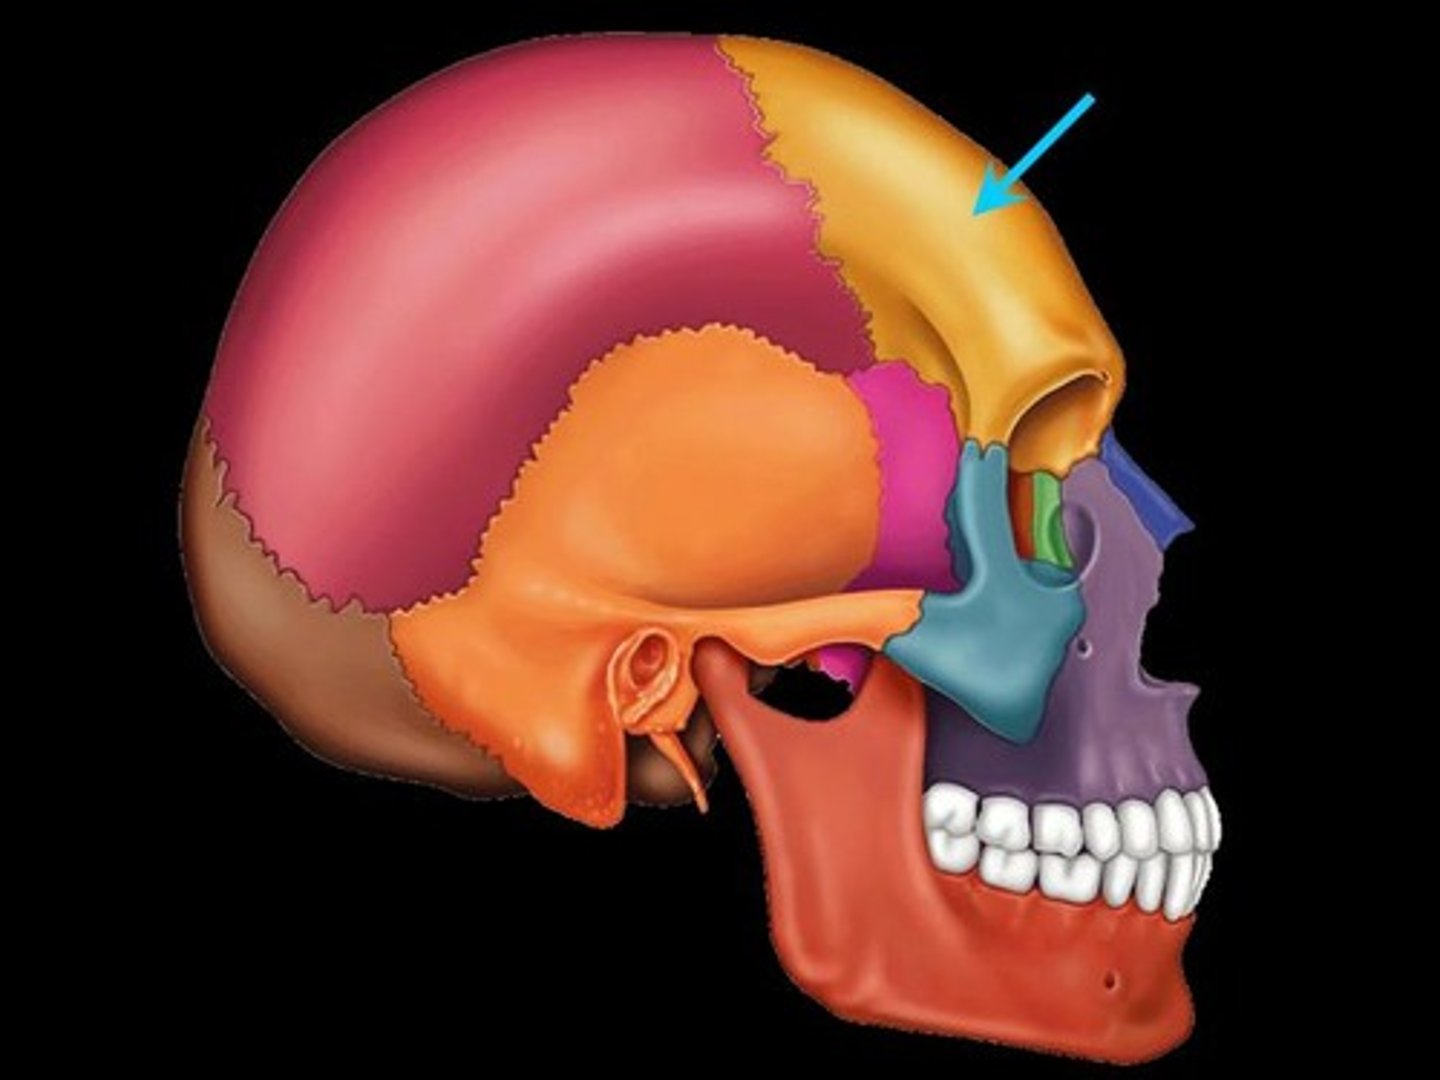

Parts of the Skull

Frontal Bone

Coronal Suture